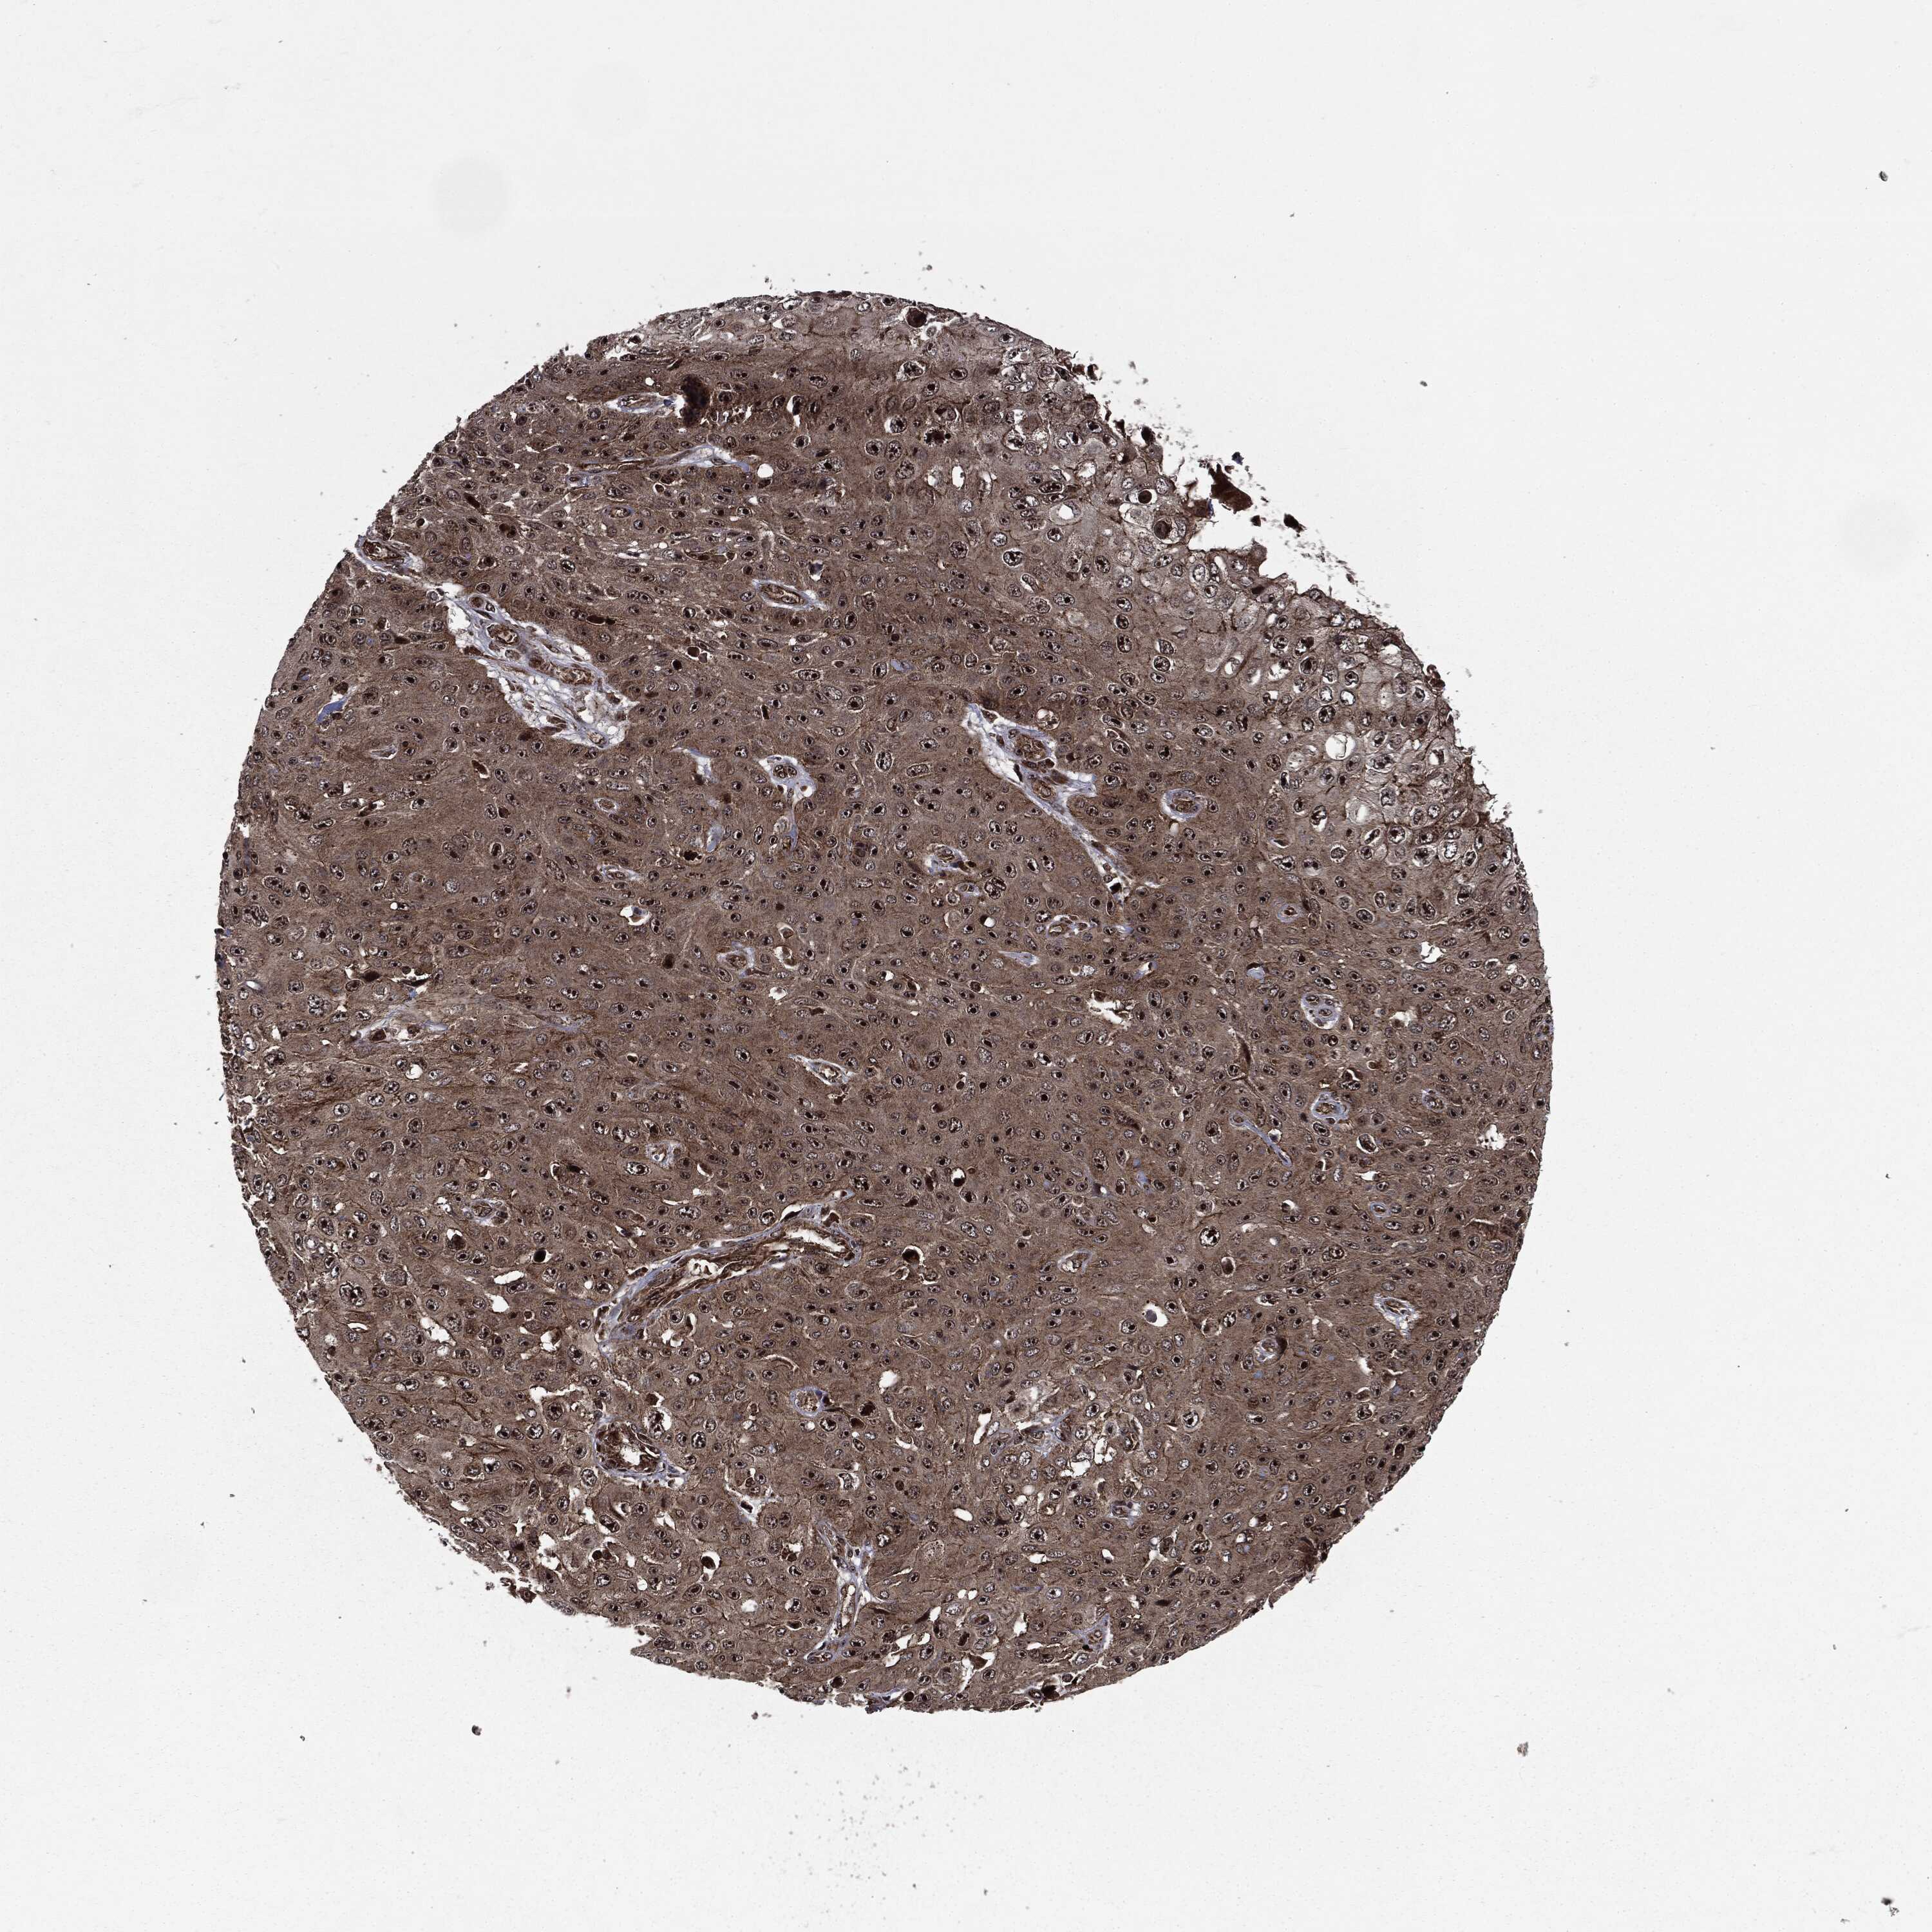

SKIN CANCER - Protein expressioni

A mouse-over function shows sample information and annotation data. Click on an image to view it in a full screen mode. Samples can be filtered based on level of antibody staining by selecting one or several of the following categories: high, medium, low and not detected. The assay and annotation is described here.

Antibody stainingi

Antibody staining in the annotated cell types in the current human tissue is reported as not detected, low, medium, or high, based on conventional immunohistochemistry profiling in selected tissues. This score is based on the combination of the staining intensity and fraction of stained cells.

Each image is clickable and will lead to virtual microscopy that enables deeper exploration of all samples and also displays staining intensity scores, fraction scores and subcellular localization as well as patient and tissue information for each sample.

Antibody HPA041933

Staining

High

Intensity

Strong

Quantity

>75%

Location

Nuclear

Basal cell carcinoma

Squamous cell carcinoma, NOS